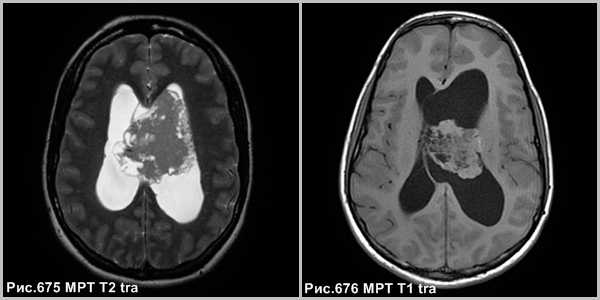

Центральная нейроцитома - кистозно-солидное объёмное образование, расположенное в боковом желудочке, связанное с прозрачной перегородкой, сопровождающееся расширением желудочковой системы (рис.677, 678).

На КТ и МРТ нейроцитомы - отграниченные образования, смешанной плотности, часто содержат кальцинаты (в 50-70% случаев) и кисты. В большинстве случаев опухоль сопровождается гидроцефалией обструктивного генеза.

Опухоль может инфильтрировать стенку бокового желудочка. В 20% случаев имеются внутриопухолевые кровоизлияния. Располагаются в просвете боковых желудочков головного мозга с тенденцией к локализации в области прозрачной перегородки и отверстия Монро.

Центральная нейроцитома в виде неоднородной структуры объёмного образования, расположенного в боковом желудочке, связанное с прозрачной перегородкой (звёздочки на рис.679-681), сопровождающееся расширением бокового желудочка (головки стрелок на рис.680, 681). МРТ демонстрирует врастание опухоли в стенку бокового желудочка левого полушария большого мозга (стрелки на рис.680, 681).